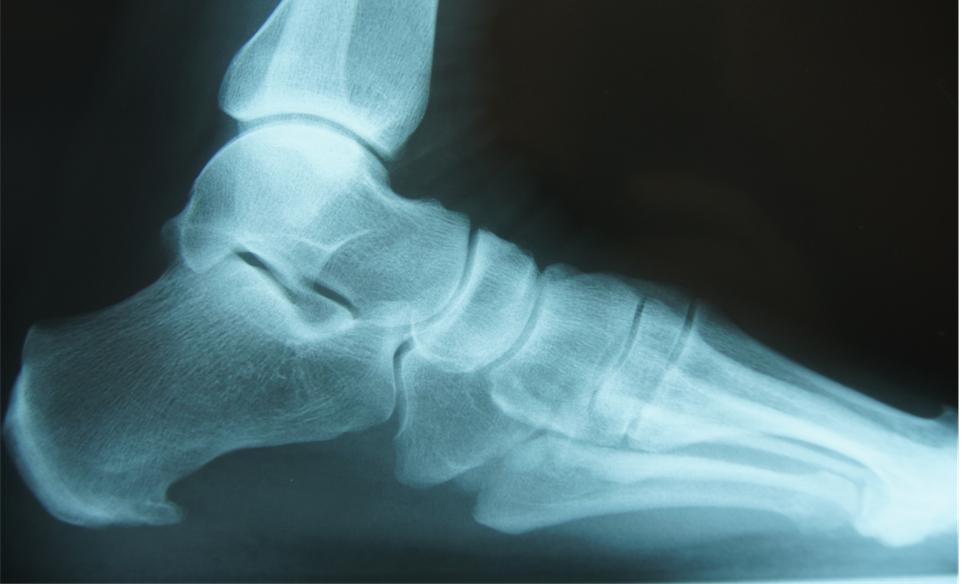

A Calcaneal spur or heel spur is a calcium deposit causing a bony protrusion (osteophyte) on your heel bone (calcaneus). It is typically detected in a radiological examination (X-ray).

A posterior calcaneal spur develops at the back of the heel and is associated with inflammation of the Achilles tendon – Achilles tendinitis. It typically causes tenderness and pain at the back of the heel, made worse by pushing of the ball of the foot.

An inferior calcaneal spur develops under the sole and is associated with inflammation of the plantar fascia but may also be associated with ankylosing spondylitis esp in children. This causes localized tenderness and pain made worse by stepping down on the heel, is worse in the morning on first stepping your heel on the floor and also increases on walking. You may not be able to bear weight on the afflicted heel comfortably. Running, walking, or lifting heavy weight may exacerbate the pain.